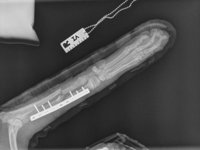

Wir treffen in Trikala, einer mittelgroßen Gemeinde auf dem griechischen Festland, ein. Vassiliki, eine 26-jährige Tierschützerin, die das Projekt an diesem Ort leitet und mich in den nächsten Tagen noch schwer beeindrucken wird, bringt uns direkt zu einer Tierarztpraxis, um Marla röntgen zu lassen. Außer den Vordergliedmaßen ist nichts gebrochen und auch die inneren Organe scheinen nicht verletzt zu sein. Dann bleibt „nur“ noch die Großbaustelle: ihre beiden vorderen Beinchen. Sie sind insgesamt an vier Stellen gebrochen. Welch himmelschreiende Ungerechtigkeit! Rechtzeitig vor einem elendigen Sterben am Straßenrand gerettet worden zu sein und dann vor nahezu unlösbaren Problemen zu stehen? Ich selber habe hier weder die Möglichkeiten, noch das Equipment, um Brüche zu operieren. Aber kapitulieren werden wir nicht. Keiner von uns. Auch Marla nicht, das haben wir uns beide ganz leise aber ganz fest versprochen.

Wenige Tage später ist Marla operiert. Mehrere Operationen waren erforderlich, um die komplizierten Brüche zu versorgen. Chirurgische Höchstleistungen machten es möglich, ihre Beine zu erhalten.